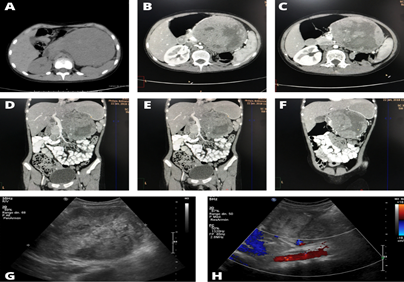

Blood tests did not show any alteration. Computed tomography (CT) of the abdomen showed a neoplastic lesion located in the left hemiabdomen measuring 14 x 12 cm, which displaced the pancreas and stomach posteriorly and showed extension to the pancreatic body and tail (Figure 1).

Neoadjuvant chemotherapy based on weekly Vincristine (1.5 mg/m2) and Actinomycin (1.35 mg/m2) was started every three weeks, with the aim of reducing the tumor volume and making it resectable. After the fourth week of treatment, a new CT scan was performed, showing the absence of tumor regression (Figure 1).

Figure 1 Comparative computed tomography (CT) findings. A: CT scan of the abdomen performed before treatment, showing an abdominal mass of 14 x 12 cm and absence of the left kidney. B-F: CT scan of the abdomen after the fourth cycle of chemotherapy, showing an abdominal mass of 14.5 x 9.25 cm, without significant changes.